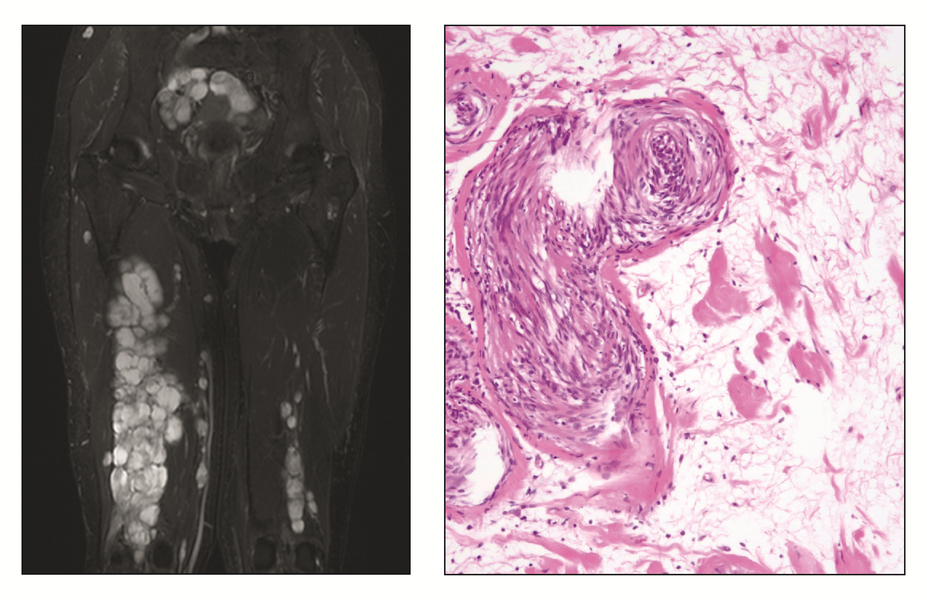

BU: Links: Ausgedehnter Tumorbefall einer Patientin mit ERBB2-mutantem Neurofibrom/Schwannom Hybridtumor in der MRT Bildgebung. Rechts: Histologisches Präparat des Hybridtumors aus Neurofibrom und Schwannom, HE-Färbung

In einigen Fällen leiden Patienten an einem sogenannten Hybridtumor, der sowohl Merkmale eines Neurofibroms als auch eines Schwannoms aufweist. Bei einer 30-jährigen Patientin haben Wissenschaftler und Ärzte das Erbgut eines solchen Hybridtumors molekular untersucht. Die Erbgut-Analyse erfolgte innerhalb der NCT/DKTK MASTER (Molecularly Aided Stratification for Tumor Eradication)-Studie. Das Programm unter Leitung der Geschäftsführenden Direktoren am Nationalen Centrum für Tumorerkrankungen (NCT) Heidelberg und Dresden, Stefan Fröhling und Hanno Glimm, richtet sich vor allem an junge Patienten mit fortgeschrittenen Krebserkrankungen und Patienten mit seltenen Tumoren (www.nct-heidelberg.de/master).

Die Forscher entdeckten im Erbgut des Tumorgewebes eine Veränderung eines Gens, das den Bauplan für den sogenannten ERRB2-Rezeptor liefert. ERRB2, auch bekannt unter dem Namen HER2, ist ein Oberflächeneiweiß, an den Wachstumsfaktoren binden und so die Zellteilung anregen. Der Rezeptor ist verstärkt auf Brustkrebszellen zu finden und wird bei dieser Erkrankung als Angriffspunkt für eine zielgerichtete Behandlung genutzt, unter anderem mit dem Tyrosinkinase-Hemmer Lapatinib. "Unsere Patientin erhielt aufgrund der identifizierten Mutation den Wirkstoff Lapatinib. Unter der Therapie wurde das Tumorwachstum gebremst, die Nervenschmerzen der Patientin konnten gelindert und die Erkrankung langfristig stabilisiert werden", berichtet Michael Ronellenfitsch, Erstautor der publizierten Ergebnisse und Leitender Oberarzt am Institut für Neuroonkologie am Universitätsklinikum Frankfurt.